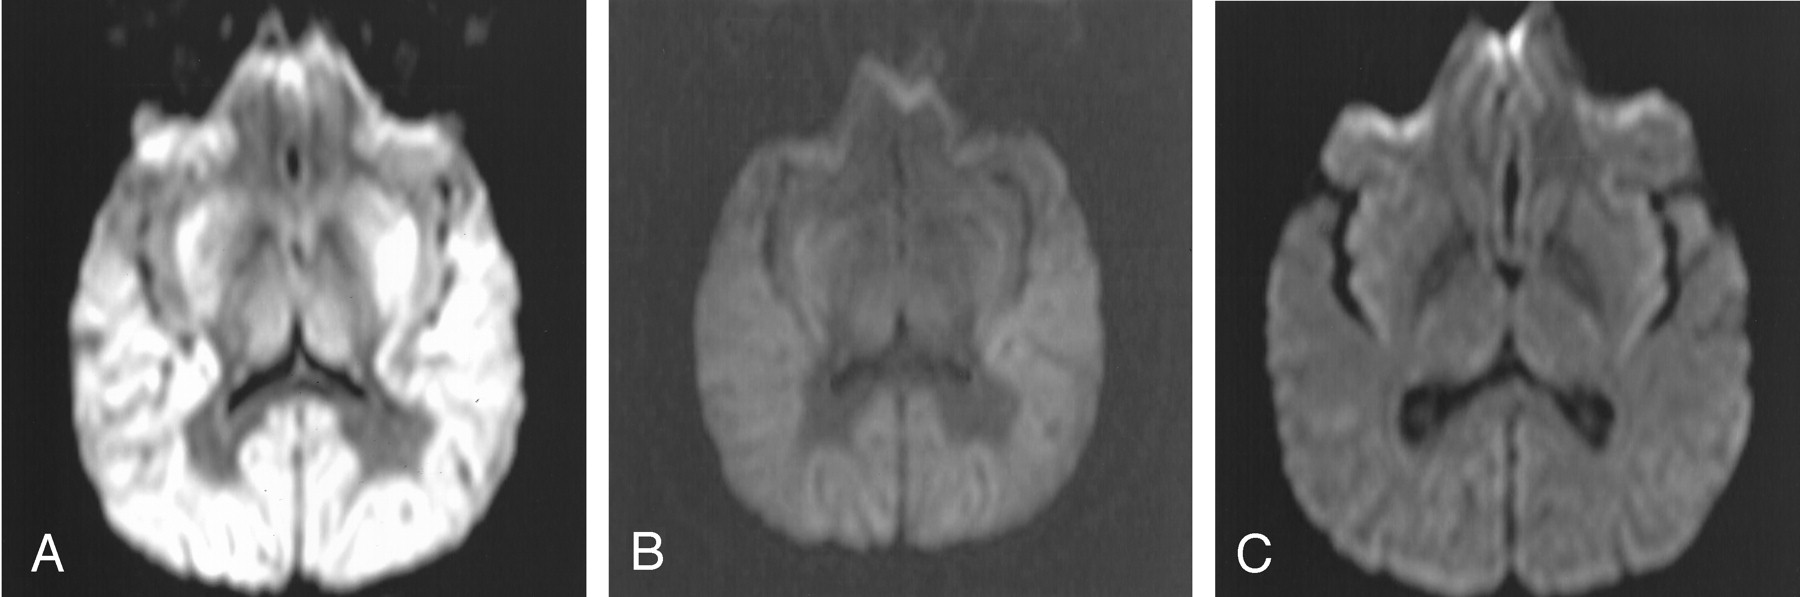

Figure 2 illustrates the findings of a properly windowed DW image in another patient (patient 5) with diffuse cortical laminar necrosis (Fig 2A) versus an improperly windowed DW image in the same patient (Fig 2B with window/level of 850/400); these two images are compared with the appearance of a properly windowed DW image in a neurologically normal 40-year-old man (Fig 2C, window/level of 250/150). Figure 2C demonstrates that there is usually only minimal gray–white matter differentiation on DW images in a neurologically normal patient.

Patient 5. Improper versus properly windowed DW images in a patient with HIE versus a properly windowed DW image in a neurologically normal 41-year-old man; all images were obtained with the same MR system. The 41-year-old patient underwent MR imaging approximately 48 hours after a global hypoperfusion-hypoxic event secondary to attempted suicide by hanging. CT scan (not shown) obtained 2 hours after the injury was interpreted as normal.

A and B, Properly windowed (250/150) DW image (A) versus an improperly windowed (850/400) DW image (B) in patient 5. Note the prominent gray–white matter differentiation even on the improperly windowed DW image in B.

C, Properly windowed DW image in a neurologically normal 40-year-old man for comparison shows that the gray–white matter differentiation is usually not so accentuated on DW images in a neurologically normal patient.